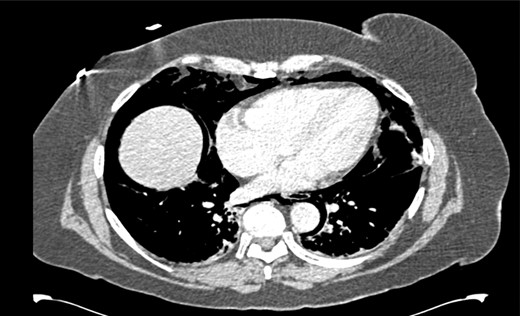

After her procedure she complained of swelling in her neck. This was not accompanied by shortness of breath, chest pain or abdominal pain. On examination, her oxygen saturation was 99% on room air, with normal respiratory and heart rate. Her respiratory examination was normal and her abdomen was soft and non-tender. She had marked crepitus over her clavicles, supraclavicular fossa and most of her neck. Her erect chest X-ray revealed air under both hemidiaphragms and significant pneumomediastinum (Fig. 1). A computed tomography (CT) scan of her chest, abdomen and pelvis was requested. This CT-scan revealed very extensive spreading of surgical emphysema in the retroperitoneum, extending into the mediastinum with small volumes of free intraperitoneal gas (Figs 2–4).

CT scan of abdomen showing free intraperitoneal gas compressing the splenic flexure.